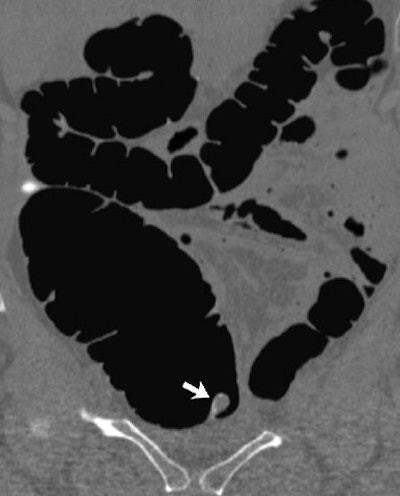

The second report was of a 58-year-old asymptomatic woman with a history of appendectomy. Routine screening VC showed a large pedunculated polypoid lesion in the cecum that demonstrated a subtle focus of internal fat attenuation on the 2D images.

"An inverted stump was prospectively suggested, but the patient still went on to same-day optical colonoscopy because a significant neoplasm could not be absolutely excluded."

The polyp was confirmed and removed at endoscopy and the polyp site cauterized, the radiologists wrote. "Although not suspected at optical colonoscopy, at pathologic evaluation the lesion was found to be an appendiceal stump."

The location and appearance of an appendiceal stump "generally allow its recognition at VC, but in some cases the possibility of a significant neoplasm cannot be completely excluded," the group concluded.